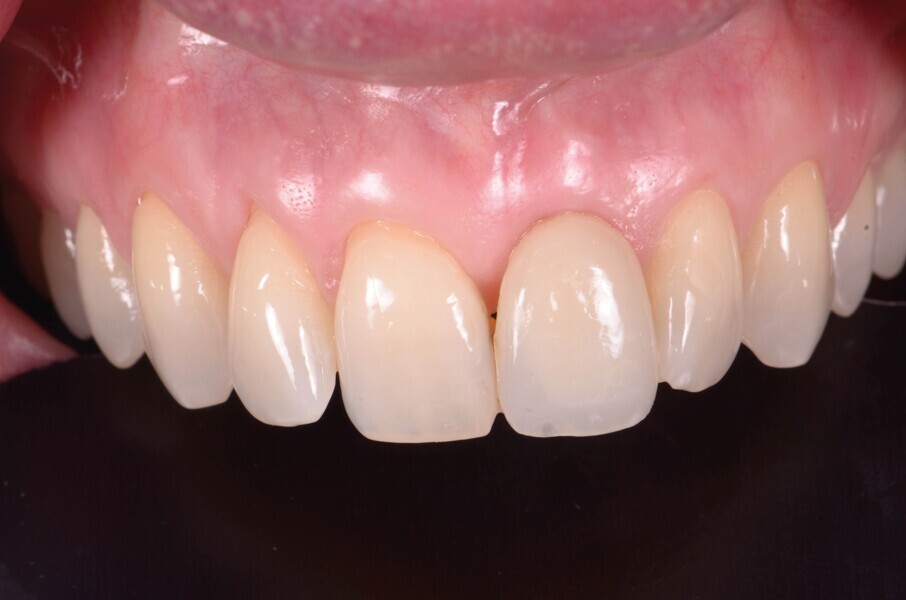

Une patiente de 42 ans est adressée au cabinet pour le remplacement de son incisive centrale supérieure gauche (dent 21) qui est à l’origine de douleurs. Un antécédent de traumatisme dentaire remontant à l’adolescence est rapporté. La ligne du sourire de la patiente est normale, mais la dent 21 est égressée (Fig. 1) La gencive présente un biotype raisonnablement épais et le feston gingival est très marque.

Fig. 1a : Vue préopératoire extraorale : lèvres au repos a

Fig. 1b : Vue préopératoire extraorale : lèvres au sourire

Fig. 2a : Vue préopératoire intraorale